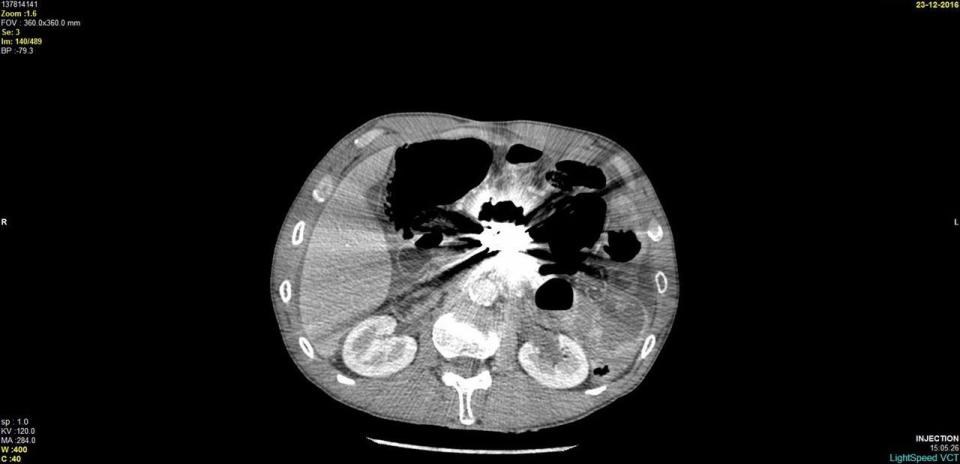

Περισσότερα από 100 κομμάτια μετάλλων διαφόρων σχημάτων και μεγεθών, τα οποία είχε καταπιεί λόγω ψύχωσης, αφαίρεσαν από το στομάχι ενός άνδρα, Γάλλοι χειρουργοί.

Σταδιακά ορισμένα μεταλλικά αντικείμενα, που είχαν χωνευθεί μόνο εν μέρει ή καθόλου, είχαν σχηματίσει ενιαίες μεταλλικές μάζες μέσα στο στομάχι του, τόσο μεγάλες που είχαν φράξει τον πυλωρό, το στόμιο που συνδέει το στομάχι με το λεπτό έντερο, πράγμα που εμπόδιζε το άδειασμα του στομαχιού του από το περιεχόμενό του.

Ο άνδρας είχε πάει πέντε φορές στα επείγοντα περιστατικά των νοσοκομείων σε διάστημα πέντε ετών, παραπονούμενος για στομαχόπονους, ναυτίες και εμετούς με αίμα. Σε τέσσερις περιπτώσεις οι γιατροί χρειάσθηκε να τον εγχειρίσουν για να αφαιρέσουν μεταλλικές μάζες από το στομάχι του, κάτι που δεν ήταν δυνατό να γίνει μόνο με το ενδοσκόπιο.

Την πέμπτη και χειρότερη φορά, πριν μερικούς μήνες, αποκαλύφθηκε ότι τα μεταλλικά αντικείμενα είχαν ανοίξει τρύπα στο στομάχι του. Οι γιατροί δήλωσαν έκπληκτοι που κάτι τέτοιο δεν είχε συμβεί πολύ πιο συχνά, αν λάβει κανείς υπόψη του τα κοφτερά αντικείμενα (π.χ. ξυραφάκια) που ο άνδρας κατάπινε. Αλλά, όπως είπαν, τα τοιχώματα του στομαχιού μπορεί τελικά να αποδειχθούν πολύ ανθεκτικά και να επουλώσουν τις πληγές τους.